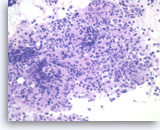

Plasma cell neoplasm,

Pancreas FNA, Direct Smear.

The aspirates show dispersed single cells with a prominent plasmacytoid appearance. The tumor cells vary slightly in size. Rare mitoses are seen.

20X

Plasma cell neoplasm,

Pancreas FNA, Direct Smear.

The aspirates show dispersed single cells with a prominent plasmacytoid appearance. The tumor cells vary slightly in size. Rare mitoses are seen.

20X

Plasma cell neoplasm,

Pancreas FNA, Direct Smear.

The tumor cells show perinuclear hof (clearing). Binucleated tumor cells are occasionally seen. Scattered lymphoglandular bodies are seen in the background.

40X

Plasma cell neoplasm,

Pancreas FNA, Direct Smear.

The tumor cells show perinuclear hof (clearing). Binucleated tumor cells are occasionally seen. Scattered lymphoglandular bodies are seen in the background.

40X

Plasma cell neoplasm,

Pancreas FNA, Direct Smear.

The tumor cells have eccentrically located round nuclei with clumped chromatin and small nucleoli.

40X

Plasma cell neoplasm,

Pancreas FNA, Direct Smear.

The tumor cells have eccentrically located round nuclei with clumped chromatin and small nucleoli.

40X

Plasma cell neoplasm,

Pancreas FNA, Cell Block.

Single tumor cells show eccentric nuclei and occasional binucleation. Flow cytometry demonstrate CD38 positive B-cells without surface immunoglobulin expression. The cytomorphologic features along with flow cytometry results are consistent with plasma cell neoplasm. CD138 immunostain can be performed on the cell block section to support the diagnosis if needed.

40X

Plasma cell neoplasm,

Pancreas FNA, Cell Block.

Single tumor cells show eccentric nuclei and occasional binucleation. Flow cytometry demonstrate CD38 positive B-cells without surface immunoglobulin expression. The cytomorphologic features along with flow cytometry results are consistent with plasma cell neoplasm. CD138 immunostain can be performed on the cell block section to support the diagnosis if needed.

40X